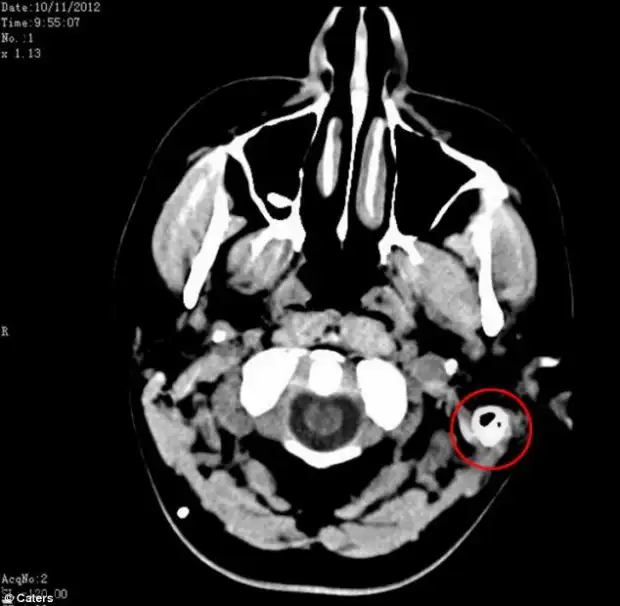

Это приводит к тому, что накапливающаяcя в черепе жидкость, давит на мозг и в крайних случаях это может даже привести к слепоте. Состояние Сэм было настолько тяжелым, что она была прикована к постели и врачи считали, что она была близка к инсульту. Но после того, как они нашли способ удалять избыток жидкости из ее мозга в желудок, ее жизнь изменилась. Слив, также известный, как желудочно-перитонеальный шунт, соединил мозг и желудок, позволяя ей переварить свою мозговую жидкость и снизить давление на мозг.

И только в мае прошлого года девушке был установлен шунт для слива лишней жидкости. Сэм надеялась на немедленное облегчение, но ее мозгу потребовалось время, чтобы привыкнуть к инородному телу. Спустя некоторое время Сэм приспособилась к изменениям и с тех пор она снова живет нормальной жизнью.